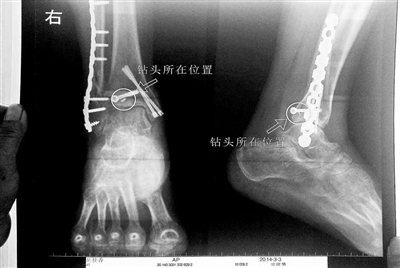

胡女士的腿部X光圖

看著X光片中自己腿內(nèi)的異物,胡女士就感到莫名的擔(dān)憂。胡女士于2013年3月在北京市豐臺(tái)區(qū)右安門醫(yī)院進(jìn)行了一次骨折手術(shù),術(shù)后醫(yī)生才發(fā)現(xiàn)手術(shù)時(shí)用來打眼用的鉆頭不慎遺留在了胡女士的骨頭中,并且無法取出。

近日,在豐臺(tái)區(qū)右安門醫(yī)院,北京青年報(bào)記者見到了胡女士,她走起路來顯得一瘸一拐,腿腳并不利索。在她帶來的X光片上,可以清晰地看到,有一個(gè)異物存在于腿內(nèi)部。

“我當(dāng)時(shí)就嚇蒙了,怎么會(huì)有一個(gè)鉆頭在骨頭里?”胡女士余悸未消地說,第二天拍攝的X光片顯示,2厘米左右的鉆頭遺留在她右腳腳踝上部的骨頭內(nèi)。

胡女士說,當(dāng)時(shí)旁邊的醫(yī)生勸慰自己,稱鉆頭留在腿里并不會(huì)有什么問題。出院后,胡女士每個(gè)月都會(huì)來醫(yī)院做復(fù)查,拍X光片。她說,每次都能夠清晰地看見自己骨頭里的那個(gè)明晃晃的“小東西”。

“留在她腿里的鉆頭確實(shí)無法取出?!毙熘魅谓忉屨f,按常理說,鉆頭不應(yīng)該斷在里面,但現(xiàn)在事情確實(shí)發(fā)生了。鉆頭沒有折在關(guān)節(jié),而是在跖骨內(nèi),跖骨主要起支撐作用,不像關(guān)節(jié)那樣起活動(dòng)作用,而且這個(gè)部位比較質(zhì)密,并非像肌肉要經(jīng)?;顒?dòng)受到擠壓。